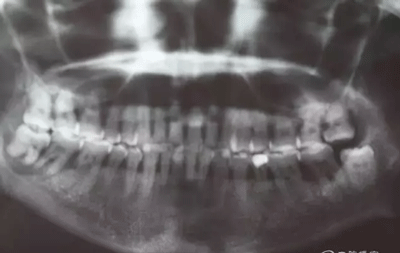

患者,白xx,女,40歲。主訴:右側(cè)下后牙牙探針齦反復(fù)腫痛,不能吃東西數(shù)月。專科檢查:48松動Ⅲ,47松動Ⅱ,牙周探針:48牙周袋均8mm,47遠(yuǎn)中牙周袋8mm,x全景片檢查:48牙槽骨弧形吸收至根尖區(qū),陰影較大。47遠(yuǎn)中牙槽骨吸收至遠(yuǎn)中根尖部,近中牙槽骨部分角形吸收。診斷:拔除48,試保留47.同期實行47牙周刮治術(shù)?;颊咄庵委煼桨福炛橥鈺?。

圖2.局部的放大影像情況。48骨質(zhì)吸收至下頜管邊緣,陰影范圍廣,拔除48后牙槽窩處理要小心。